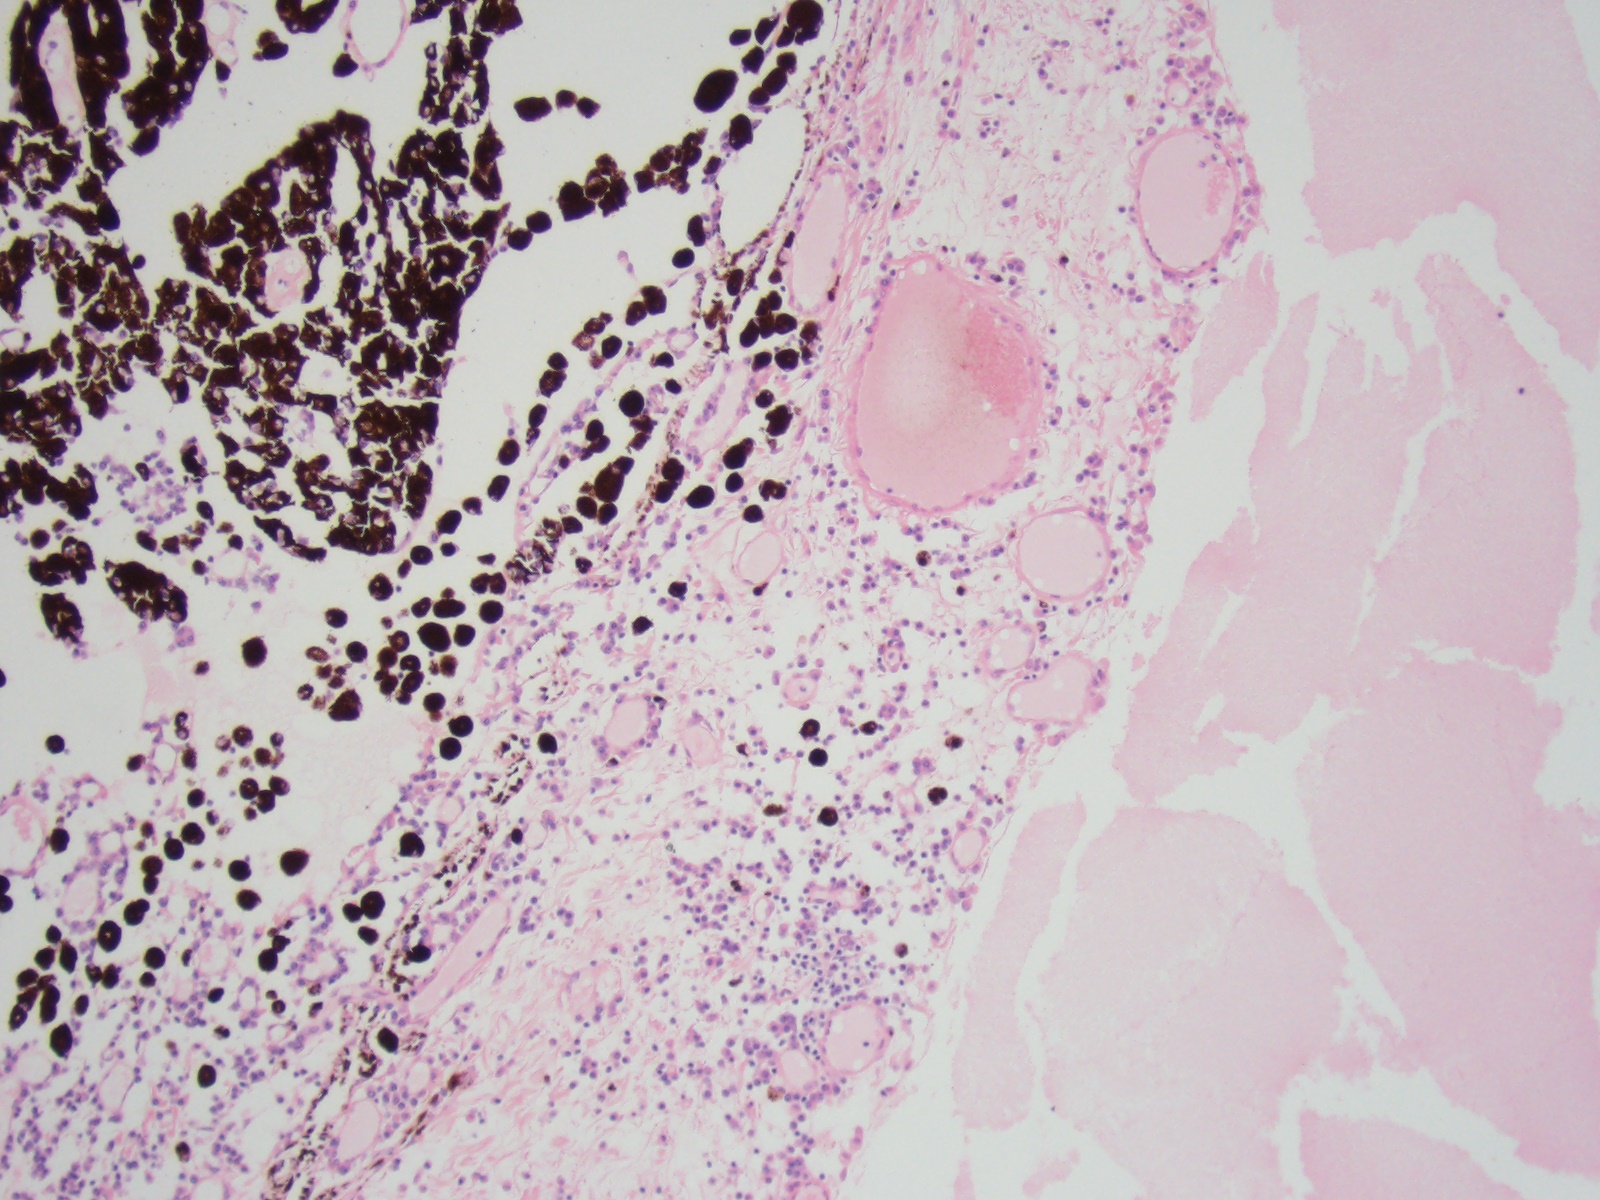

Higher magnification view of preiridal fibrovascular membrane composed of large vascular channels, fibroblasts and loose fibrous connective tissue infiltrated by lymphocytes and plasma cells.